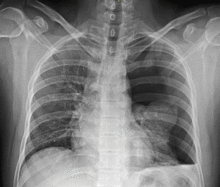

Chest X-ray showing a pneumothorax on the right (left in the image), where the absence of lung markings indicates that there is free air inside the chest

Chest X-ray

Chest X-ray of left-sided pneumothorax (seen on the right in this image). The left thoracic cavity is partly filled with air occupying the pleural space. The mediastinum is shifted to the opposite side.

Chest X-ray showing the features of pneumothorax

Traditionally a plain radiograph of the chest, ideally with the X-ray beams being projected from the back (posteroanterior, or "PA"), has been the most appropriate first investigation. These are usually performed during maximal inspiration (holding one's breath); no added information is gathered by obtaining a chest X-ray in expiration (after exhaling).[12][13] If the PA X-ray does not show a pneumothorax but there is a strong suspicion of one, lateral X-rays (with beams projecting from the side) may be performed, but this is not routine practice.[13][17] It is not unusual for the mediastinum (the structure between the lungs that contains the heart, great blood vessels and large airways) to be shifted away from the affected lung due to the pressure differences. This is not equivalent to a tension pneumothorax, which is determined mainly by the constellation of symptoms, hypoxia, and shock.[12]

The size of the pneumothorax (i.e. the volume of air in the pleural space) can be determined with a reasonable degree of accuracy by measuring the distance between the chest wall and the lung. This is relevant to treatment, as smaller pneumothoraces may be managed differently. An air rim of 2 cm means that the pneumothorax occupies about 50% of the hemithorax.[13] British professional guidelines have traditionally stated that the measurement should be performed at the level of the hilum (where blood vessels and airways enter the lung) with 2 cm as the cutoff,[13] while American guidelines state that the measurement should be done at the apex (top) of the lung with 3 cm differentiating between a "small" and a "large" pneumothorax.[23] The latter method may overestimate the size of a pneumothorax if it is located mainly at the apex, which is a common occurrence.[13] The various methods correlate poorly, but are the best easily available ways of estimating pneumothorax size.[13][17] CT scanning (see below) can provide a more accurate determination of the size of the pneumothorax, but its routine use in this setting is not recommended.[23]

Not all pneumothoraces are uniform; some only form a pocket of air in a particular place in the chest.[13] Small amounts of fluid may be noted on the chest X-ray (hydropneumothorax); this may be blood (hemopneumothorax).[12] In some cases, the only significant abnormality may be the "deep sulcus sign", in which the normally small space between the chest wall and the diaphragm appears enlarged due to the abnormal presence of fluid.[14]